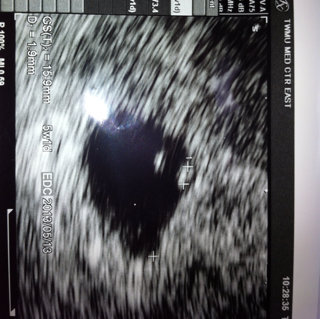

妊娠5週 赤ちゃん-妊娠5週目のママの様子と赤ちゃんの様子をみてみましょう。 妊娠5週のママの状態 カラダの見た目はかわりませんが、ホルモンレベルの変化により、すでにカラダの不調を感じているママもいるでしょう。 微量の出血があった?妊娠5週初期では、まだ超音波検査の画像では赤ちゃん(胎芽)が見えていないことが多いです。 妊娠5週後半になると、赤ちゃんが見え始めてきます。 妊娠6週の⼤きさ 胎嚢は15cmほどになり、胎嚢の中の白っぽい円も大きくはっきりと見えるようになり

妊娠5週6日 5w6d の超音波 エコー 写真

妊娠5週目 胎嚢の大きさ エコー写真 つわり症状や流産のこと 妊娠初期 All About